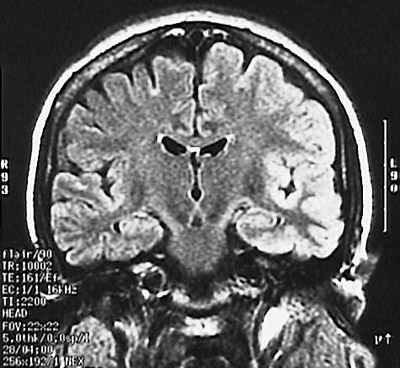

This cerebral MRI scan in coronal view demonstrates markedly abnormal signal hyperintensity, mainly in the left temporal lobe and adjacent insular cortex. This is consistent with a diffuse viral encephalitis.